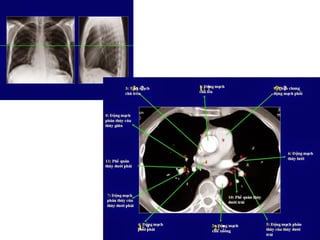

CAÙC MAËT CAÉT CÔ BAÛN TRUNG THAÁT

1. Ngang möùc khôùp öùc ñoøn

5 maïch maùu : 3 ñoäng maïch phiaù sau (döôùi ñoøn (s) caûnh (c), thaân caùnh tay

ñaàu (b) vaø 2 tónh maïch phiaù tröôùc thaân caùnh tay ñaàu (P) vaø (T) (bv)

Löu yù caùc beänh lyù: maïch maùu (phình-daõn maïch..), u, haïch